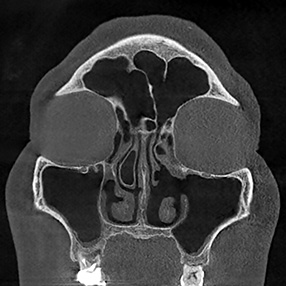

※ 축농증 수술 후 생길 수 있는 부작용으로는 출혈, 감염, 염증이 있을 수 있습니다.

본 사진은 의료기관에서 진료를 본 환자이고, 전후 사진 인물이 동일인이며,동일조건에서 촬영이 되었습니다.